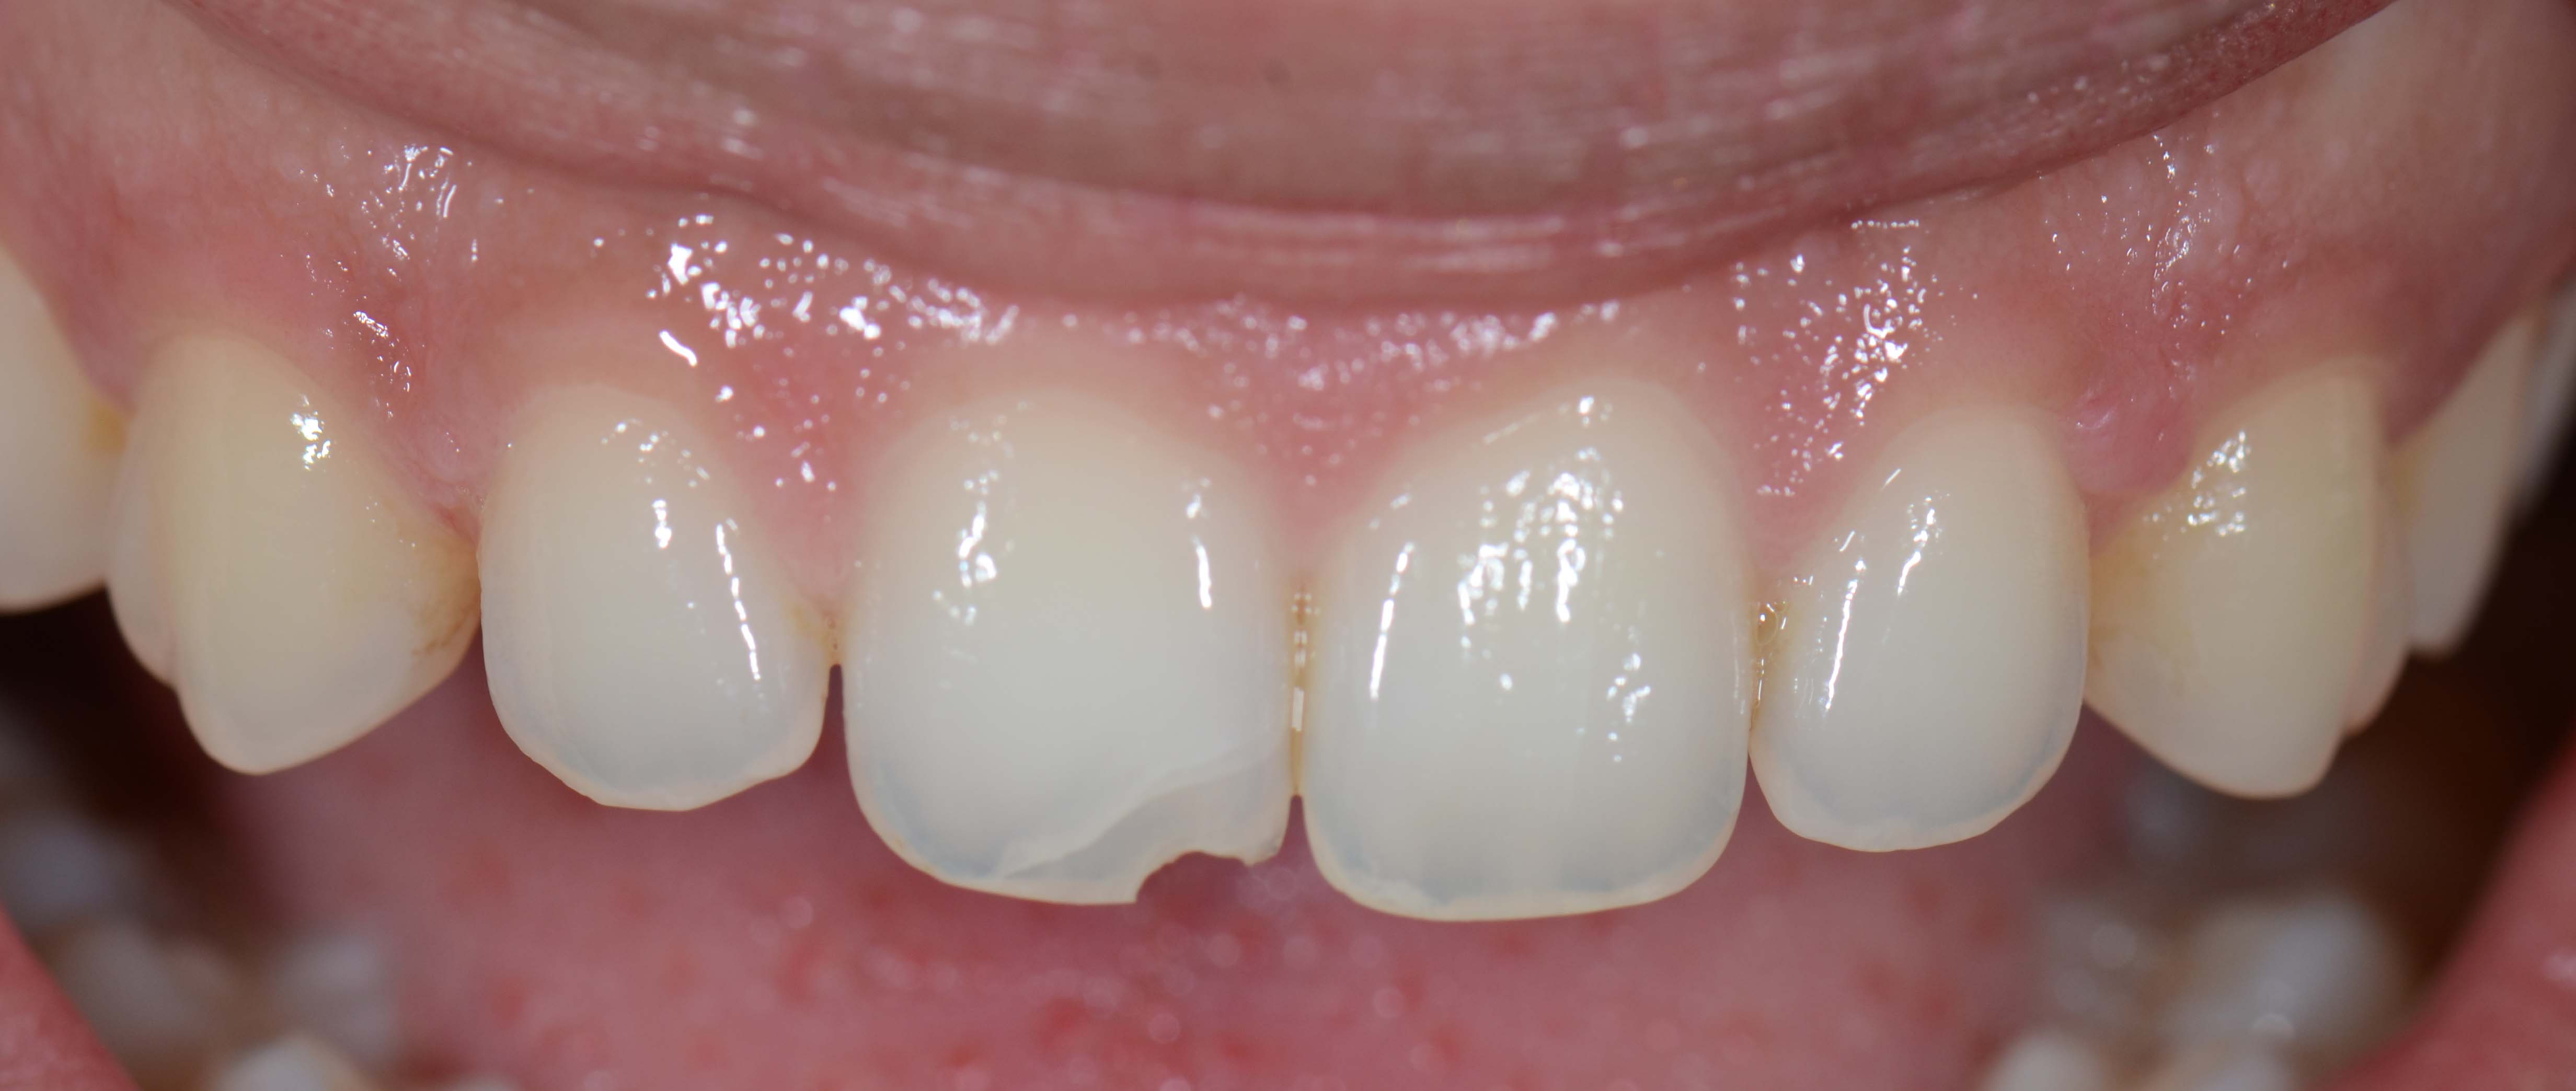

• Photos

Urgent treatments are executed if necessary as in the case on the left.

SOS